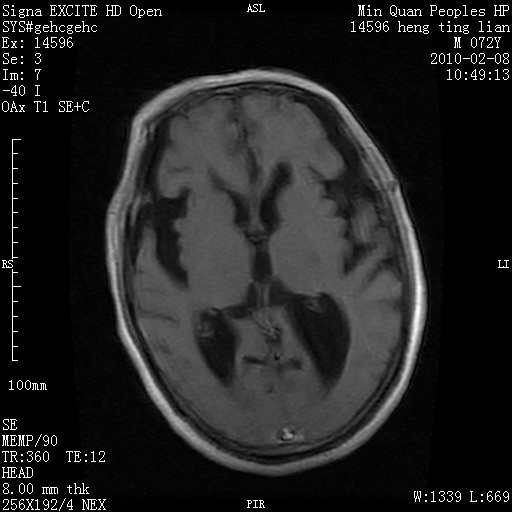

m,72,头疼,头晕两年,伴视力模糊三月,饮食呛咳两天。pe:颈部抵抗,左眼突出,左眼瞳孔约3mm,对光反射消失,双眼失明,伸舌困难,双肺呼吸音粗,心率110次/分,左上肢肌力i级,左下肢屈曲,肌张力高。现有08年2月19mri平扫及10年2月8日mri增强请会诊。ct病灶呈低密度伴散在点、片状等密度区,无明确钙化(无ct片资料可供上传)。[

脑外肿瘤,囊实性,环状不规则强化,内听道扩大,考虑神经源性肿瘤

左侧桥小脑区占位伴梗阻性脑积水----考虑 1神经鞘瘤 2室管膜瘤。

左侧桥小脑区神经鞘瘤伴梗阻性脑积水。

脑外肿瘤,病灶呈匍匐蔓延,表皮样囊肿可能性大。